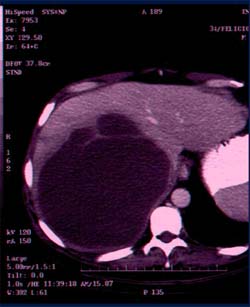

IMAGEM DESTE NÚMERO

Imagem tomográfica do abdome evidenciando

um abscesso hepático.

Observação: Drs. Denise Paranaquá Vezozzo e Sérgio Barbosa Marques.